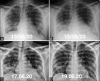

Purpose: The purpose of this study was to analyse the patterns of radiological findings on chest radiograph (CXR) for suspected and confirmed COVID-19 patients on initial presentation to the emergency medical services (EMS) on admission and to assess the progression and resolution.

Results: 756 RT-PCR confirmed COVID-19 patients were included in our study who had initial CXR. 510 (67.46%) of our patients with positive initial RT-PCR showed abnormal baseline CXR. The abnormal findings were described as haziness akin to ground glass opacities (GGO) on CT, peripheral opacities, patchy parenchymal opacities and consolidation. Peripheral opacities and lower zone distribution were the commonest pattern of CXR abnormalities with bilateral involvement. The severity of findings on serial CXR and radiographic regression was studied along with follow-up to assess response to treatment. Forty-six patients showed features of acute lung injury (ALI). Complications and new CXR findings were reported for patients who were given ventilator support.

Conclusion: CXR is a valuable baseline radiological investigation on hospital admission in symptomatic patients with suspected or confirmed Covid-19 presenting to the EMS as it helps to monitor the progress and regression of the disease in conjunction with clinical findings.